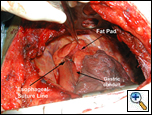

The fat pad is also useful in protecting bronchial suture/staple lines in patients who have undergone

| Figure 2: Buttress of esophageal suture line. |

neoadjuvant chemoradiation or have had previous radiation to the bronchus, and in patients who will undergo postoperative radiation of the mediastinum [3]. Lastly, esophageal suture lines may be buttressed using a pericardial fat pad flap (Figure 2).